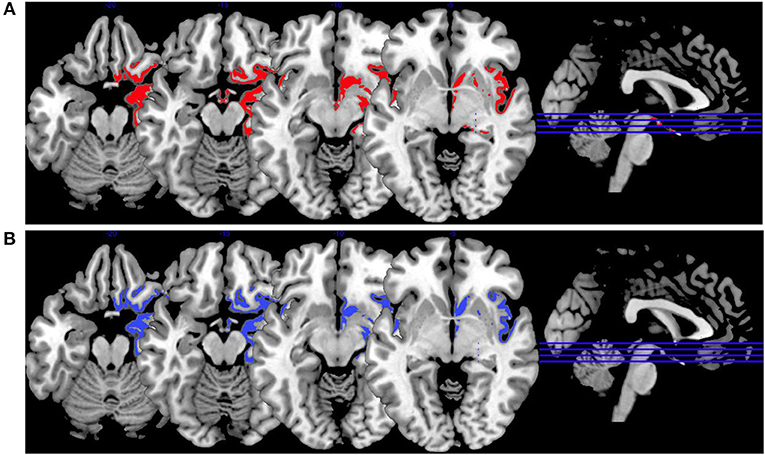

Synthesis of Findings From Studies Using Emotion Induction Paradigms

In Figure 4, we provide an overview on activation patterns during emotion induction over all reviewed studies. As with the other multislice activation pattern figures, this can be helpful to enable a synthesis of findings across the published studies. However, the emotion induction tasks used in the different studies vary considerably, and therefore this synthesis of the findings may be of limited use and must be interpreted with caution.

Figure 4. Emotion induction activations. Overview of the working memory brain activation patterns reported by the reviewed studies. Hyperactivations are shown in red, hypoactivations in blue. (A) shows the activation patterns in the group comparison VS vs. NVS with VS>NVS in red (shown slice numbers are 100, 110, 120, 130) in the contrasts shock anticipation phase II (last 21 s after threatening with an electric shock) vs. shock anticipation phase I (first 9 s after threat) and negative vs. neutral emotional pictures and neutral emotional pictures vs. rest, (B) shows the activation patterns in the group comparison VS vs. HC with VS>HC in red (shown slice numbers are 100, 110, 120, 130) in the contrasts shock anticipation vs. safe condition and in negative vs. neutral emotional pictures contrast and neutral emotional pictures vs. rest, (C) shows the activation patterns in the group comparison NVS vs. HC with NVS>HC in red (shown slice numbers are 170, 180, 190, 200) in the contrast negative vs. neutral emotional pictures and NVS<HC in blue (shown slice numbers are 160, 170, 180, 190) in the contrast positive vs. neutral emotional pictures, (D) shows the activation patterns in the group comparison NVS high vs. low aggression with NVS high>NVS low in red (shown slice numbers are 100, 110, 120, 130) in the contrast of hearing emotional words (positive and negative ones) vs. rest.

Figure 4A shows the group comparison of violent vs. non-violent persons with schizophrenia over all emotion induction tasks. Only hyperactivations in the right middle frontal gyrus, inferior frontal gyrus, medial prefrontal gyrus, anterior cingulate, lingual gyrus, globus pallidus, mid-cingulate, precuneus, cuneus, middle temporal gyrus, inferior temporal gyrus and in the left middle occipital gyrus, and cerebellar tuber were reported in this group comparison.

When comparing VS with HC, as shown in Figure 4B, only hyperactivations can be found. Mainly, the right hemisphere is activated (middle frontal gyrus, parahippocampal gyrus, middle occipital gyrus, anterior cingulate gyrus, cuneus, superior parietal gyrus)—hyperactivations are also seen bilaterally in the superior frontal gyrus, lingual gyrus, fusiform gyrus, superior temporal gyrus and in the left precentral gyrus, caudate nucleus, postcentral gyrus, and inferior occipital gyrus. When comparing NVS with HC (Figure 4C), there were hyperactivations in the left cerebellum and the left inferior parietal lobe and a hypoactivation in the lingual gyrus.

The activation patterns in Figure 4C differ considerably from the ones shown in the group comparison VS vs. HC in Figure 4B—we therefore suspect that emotion networks in particular may play an important role in patients with schizophrenia and aggression when in comparison with NVS. However, further studies with higher methodological quality and replication studies using comparable emotion induction paradigms are needed to test this hypothesis.

When comparing high vs. low aggressive NVS in emotion induction paradigms (Figure 4D), authors reported hyperactivation in the right superior frontal gyrus and the left hippocampus. However, it remains unclear whether these activation patterns are specific for aggression.

Synthesis of Findings From Studies Using Affective Theory of Mind Paradigms

In Figure 5, we provide an overview on activation patterns generated by affective theory of mind paradigms. The only study reporting on this area was performed by Schiffer et al. (36). Hyperactivations were present in the left inferior frontal gyrus and the left superior temporal sulcus reported in the group comparison of violent as opposed to non-violent persons with schizophrenia. Here, activation of the inferior frontal gyrus is compatible with a challenge in language comprehension, while the superior temporal sulcus is known to be implicated in social perception and general theory of mind.

Figure 5. Affective theory of mind activations. Overview of the affective theory of mind brain activation patterns reported by the reviewed studies, the group comparison being VS vs. NVS in the contrast of mental state attribution vs. gender discrimination. Here, we show the hyperactivation of VS>NVS in red (shown slice numbers are 170, 180, 190, 200).